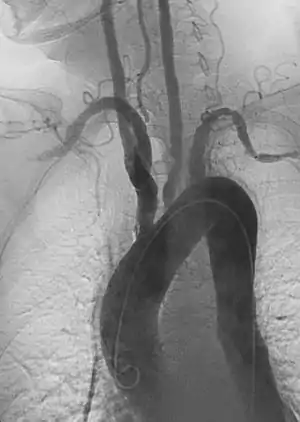

Durante o exame físico uma diferença entre os pulsos radiais esquerda e direita podem ser percebidos, geralmente um dos pulsos está ausente e o outro aumentado. A estenose dos ramos da aorta afetados pode ser auscultada. Estudos de imagem (como ressonância magnética, raios-X e angiogramas), que mostram a localização e a gravidade da inflamação e aneurismas nas artérias.[6]